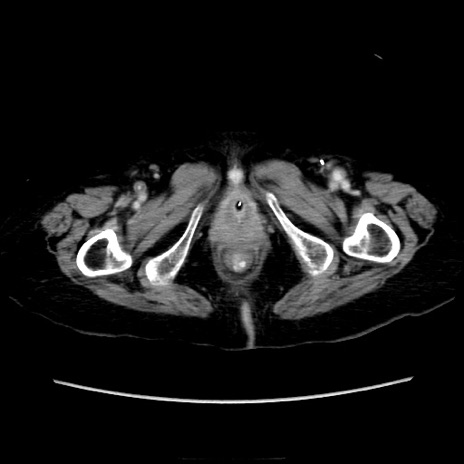

症例40(横断像)

【症例】90歳代女性

【主訴】腹痛・嘔吐

【現病歴】 食欲低下、嘔吐があり昨日他院受診。肺炎と診断され入院となる。入院後より腹部全体に圧痛あり。胃管留置され経過みていたが、症状持続するため、

当院転院となる。

【既往歴】胸椎圧迫骨折、胆石症

【身体所見】腹部:中央に激痛あり、圧痛あり、反跳痛不明

【データ】WBC 17100、CRP 18.82

横断像